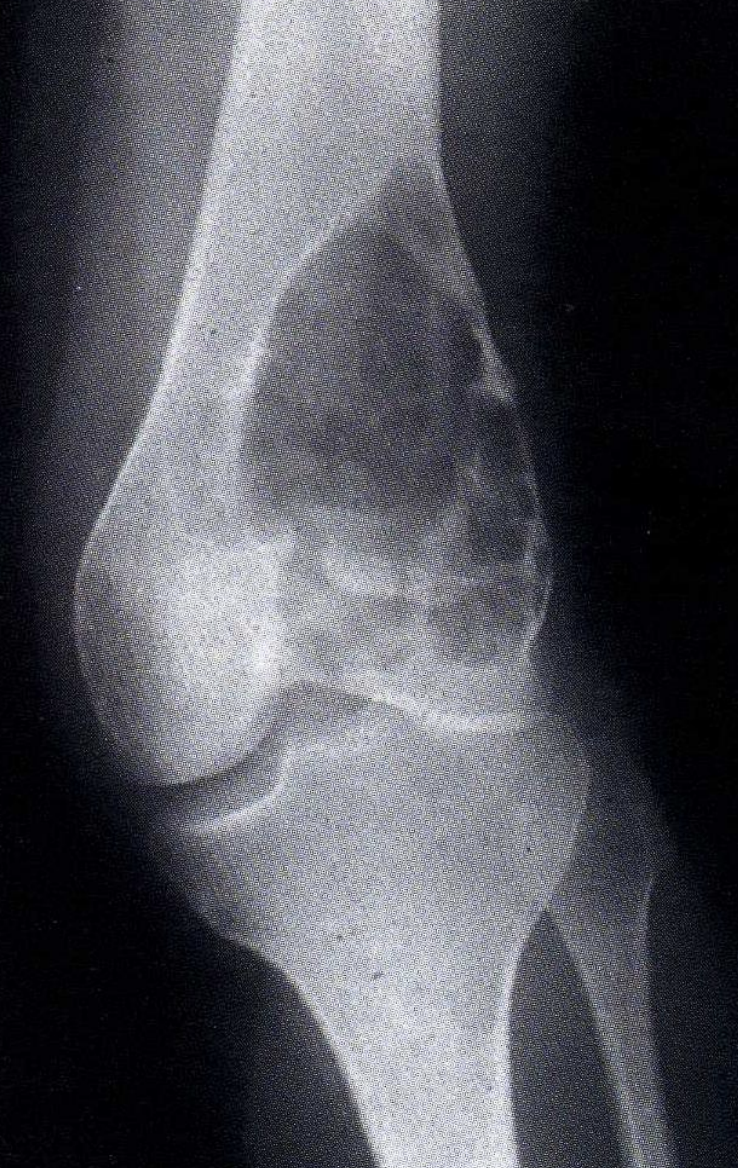

What is the x-ray appearance of a giant cell tumour?

Lytic/lucent lesions right up to articular surface (usually non-invasive)

What is the site distribution of Giant cell tumour?

Commonest Knee-epiphesis